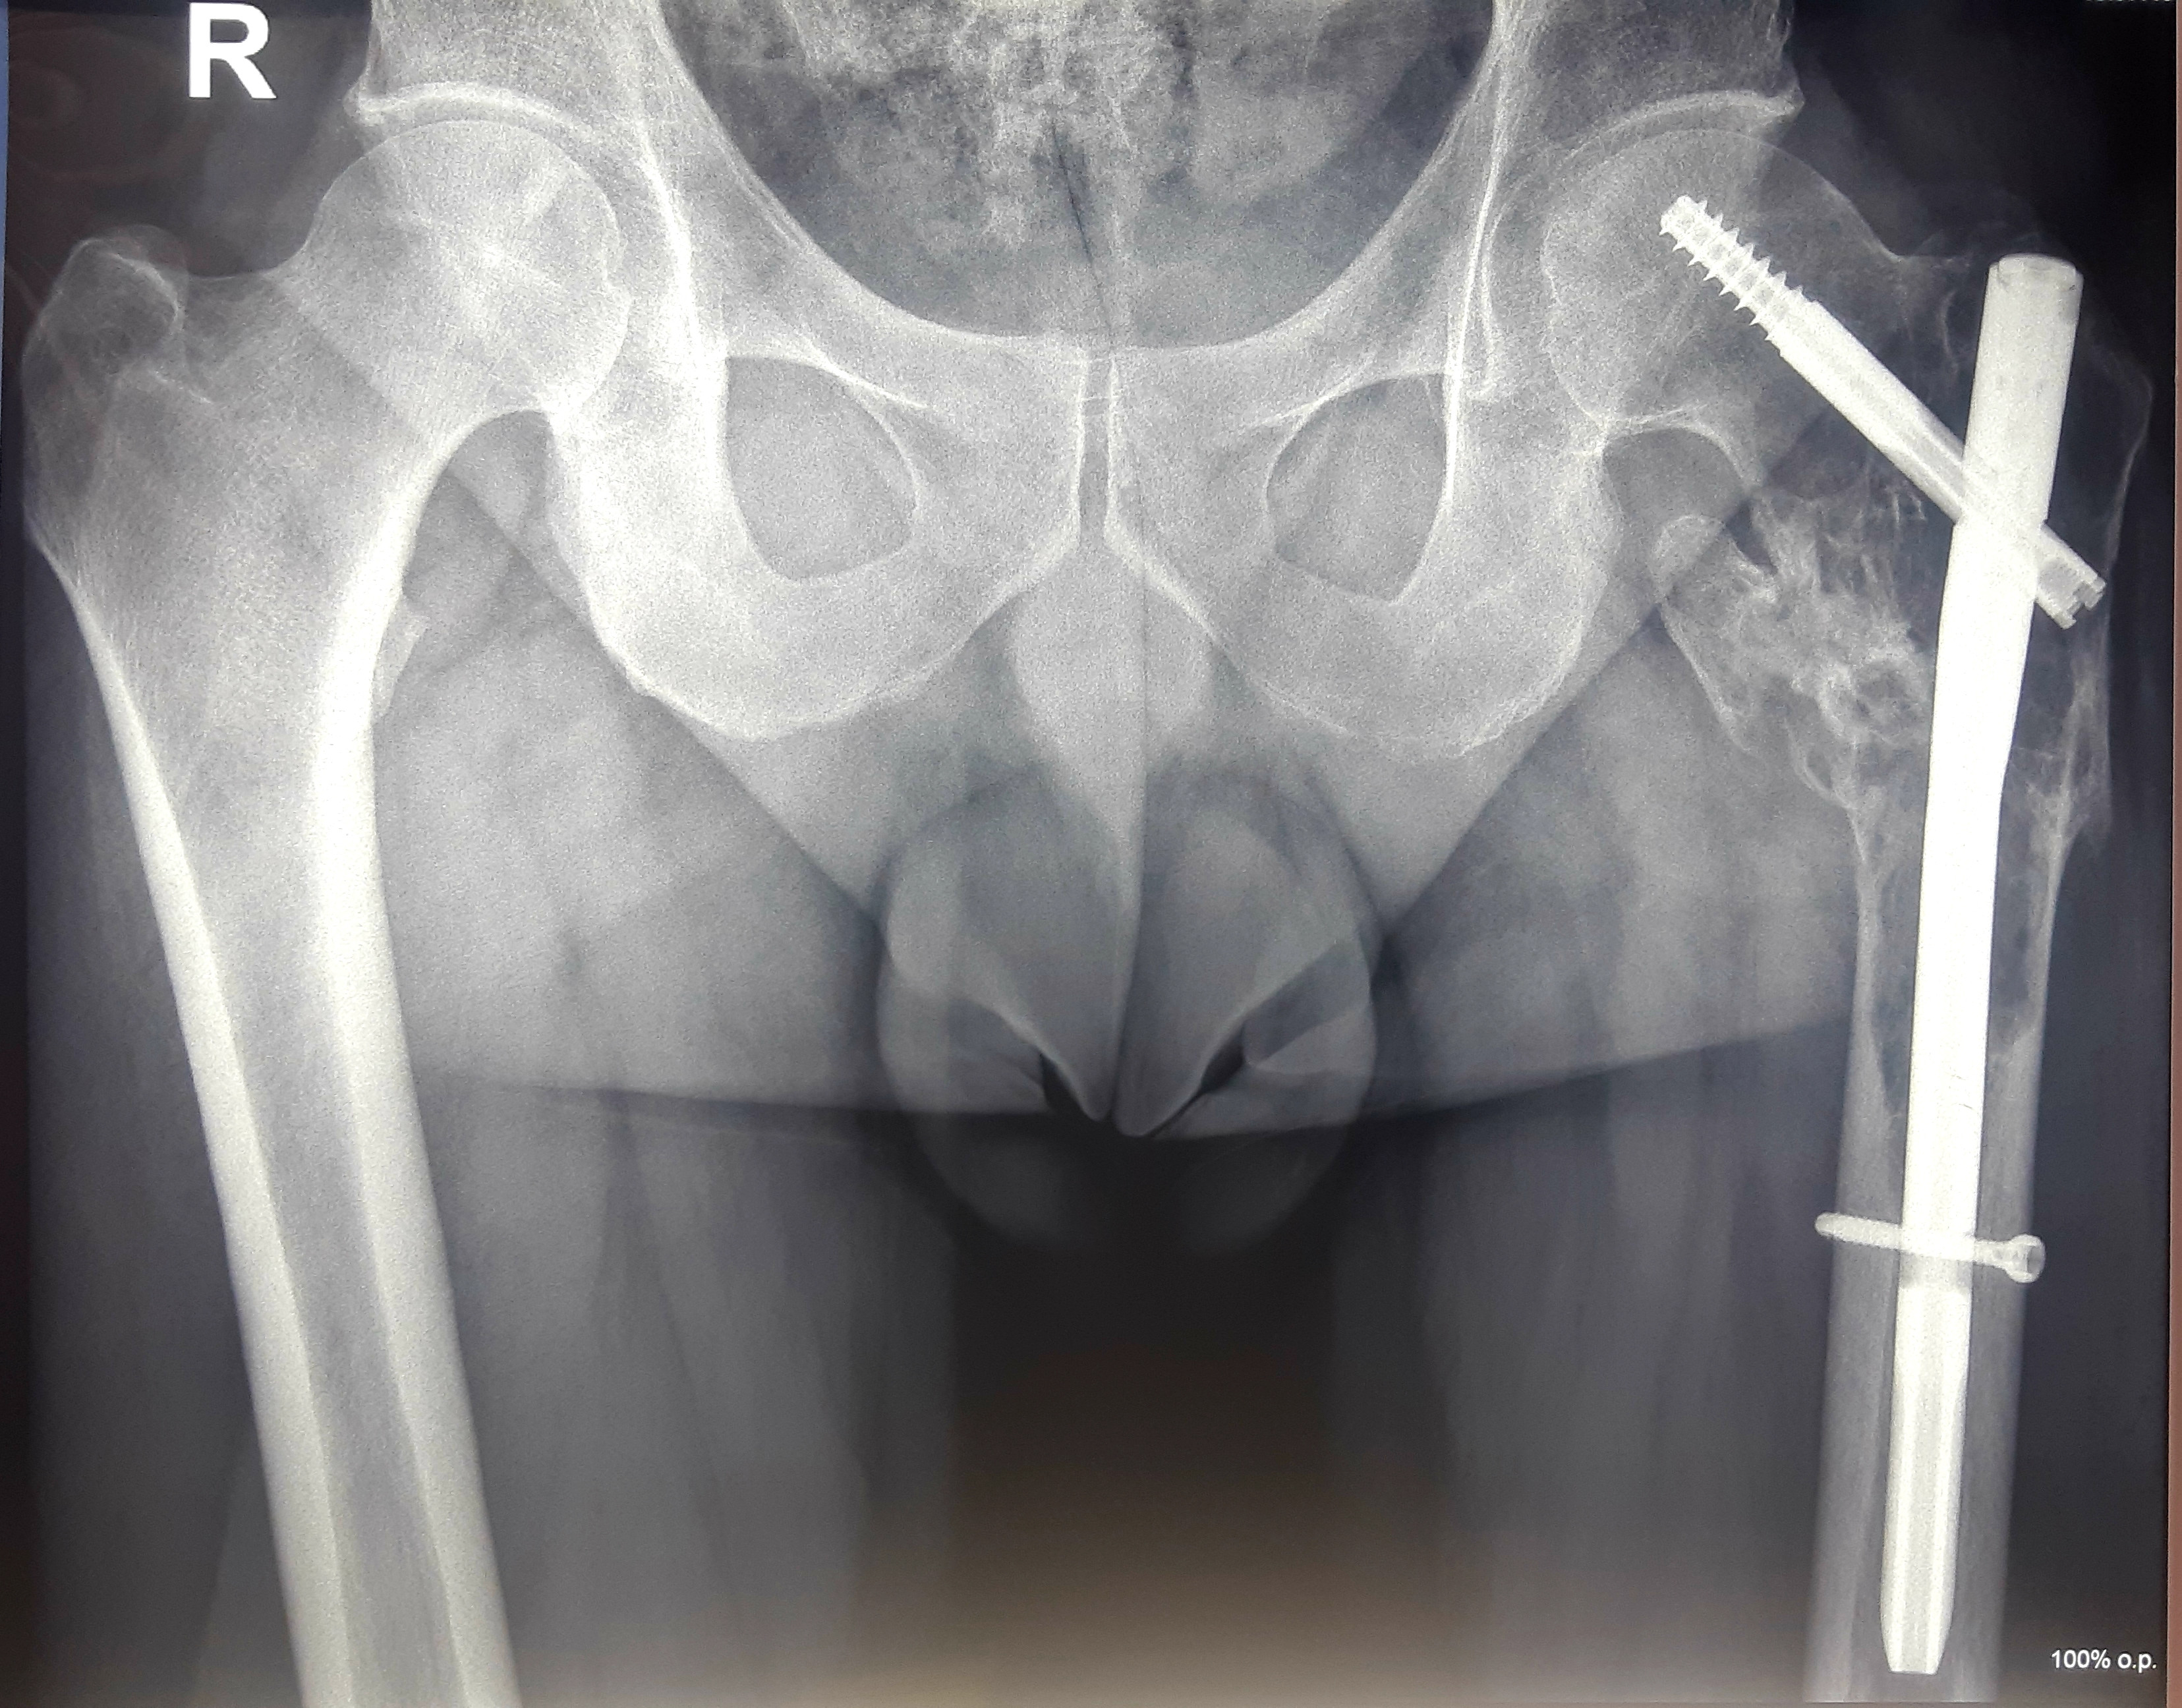

1. Солитарная плазмоцитома верхней трети бедренной кости.

После хирургического лечения в одной из зарубежных клиник по поводу перелома бедренной кости, как впоследствии оказалось, вторичного характера, 40-летний пациент обратился в МЦ ''Наири''.

В ходе обследования была диагностирована солитарная плазмоцитома.

После проведения предоперационной химиотерапии пациент был прооперирован – была произведена сегментарная резекция верхней трети бедренной кости, образовавшийся дефект был замещен индивидуальным биполярным эндопротезом бедренной кости и тазобедренного состава, изготовленным на заказ в Европе. В результате проведения органосохранного лечения удалось сохранить функционирующую конечность пациента.

До операции

После операции